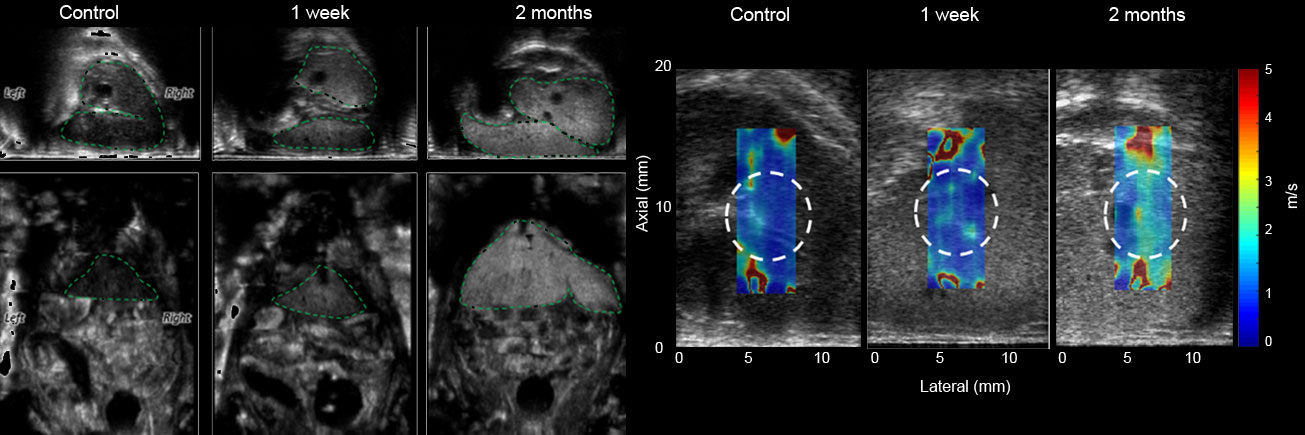

- Elastografia: badanie sztywności tkanek za pomocą fali ścinającej (Shear Wave Elastography) np. zwłóknienia wątroby

Angiografia akustyczna: umożliwia obrazowanie z dużą czułością układu mikrokrążenia guzów lub narządów i może być wykorzystywane do oceny angiogenezy guza oraz badania odpowiedzi na leczenie lub zmian uszkodzeń w tkance w czasie.

- Zautomatyzowane pozycjonowanie przetworników pozwala na skanować czołowe, strzałkowe i osiowe płaszczyzn ortogonalnych całego ciała, generując obrazy 3D o wysokiej rozdzielczości, które bardziej przypominają obrazy MRI niż tradycyjne USG.